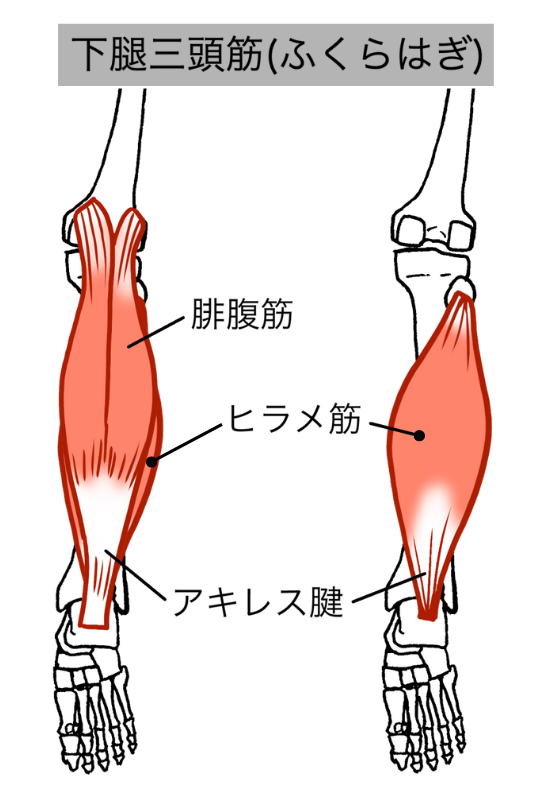

・硬くなったふくらはぎや足首の筋肉を緩め、腱への負担を軽減